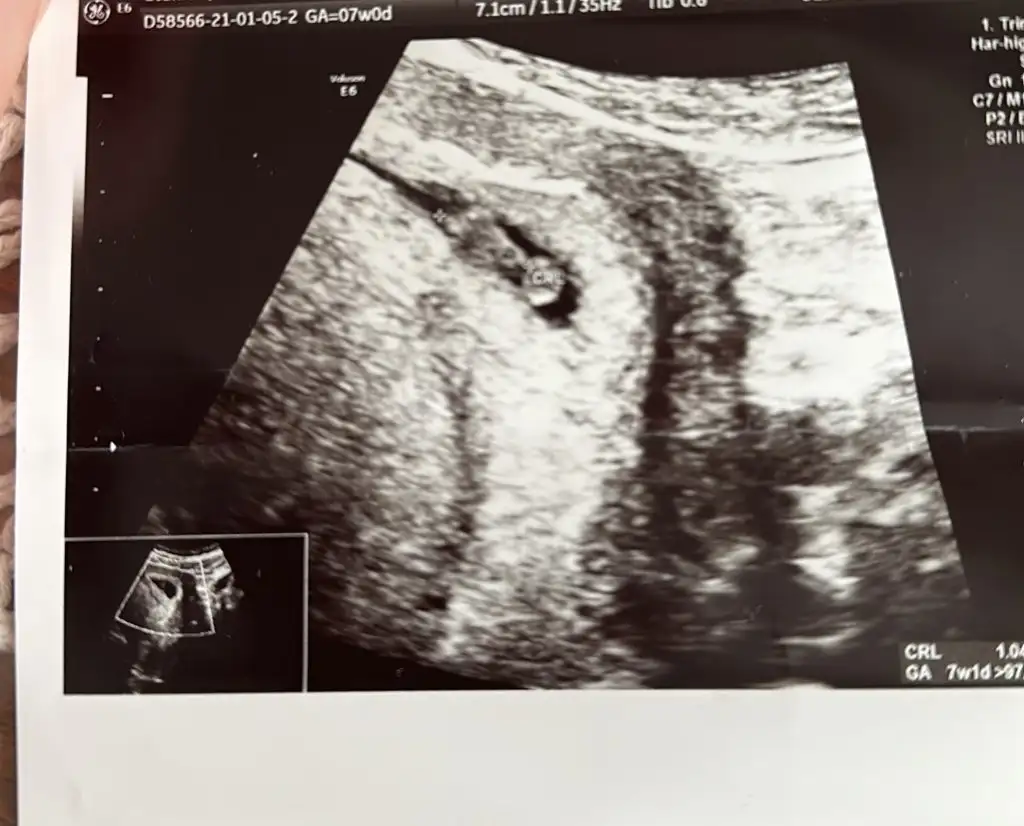

Şimdi 6+3te bebişi gördük, kalp atışını duyduk hem de maşallah baya gümbür gümbür